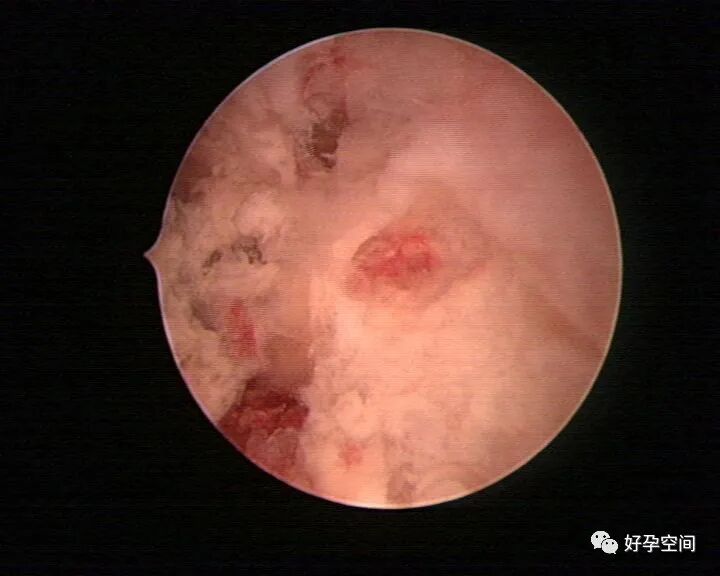

病例16:棉絮状干酪样坏死组织